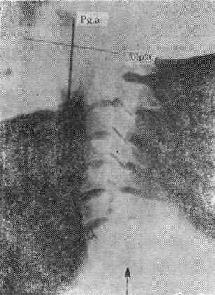

气道肿<a href=瘤(两箭头之间)"/>

113-3 气道肿(两箭头之间)

(四)占位性病变 ①血肿、脓肿是较常见的原因,如咽后壁脓肿;②肿(图113-37),管腔内或管壁良恶性肿如错构、血管等;③气道附近组织器官的肿,如甲状腺的肿压迫侵犯气道。这类原因引致的气道梗阻,一般是慢性进行性的。然而当气道狭窄的程度超过管径的75%以上,由于附加因素如粘痰等可导致急性气道梗阻,产生严重的呼吸困难,甚至窒息死亡。④异物吸入气官。

(三)X线观察①咽喉部侧位要注意咽喉颈段气管腔道的形态,有无异常的阴影;②胸腔入口区要注意气管形态改变,有无压迫移位及异常软组织影;③气管肿虽然是一种慢性生长的占位性病变,当病变增长占居管腔的75%以上时,由于附加因素如粘痰等可引致急性呼吸道梗阻的症状-阻塞性呼吸困难,如气管错构;④咽部径线和横断面积(CT片)测量,对诊断呼吸睡眠综合征有帮助。